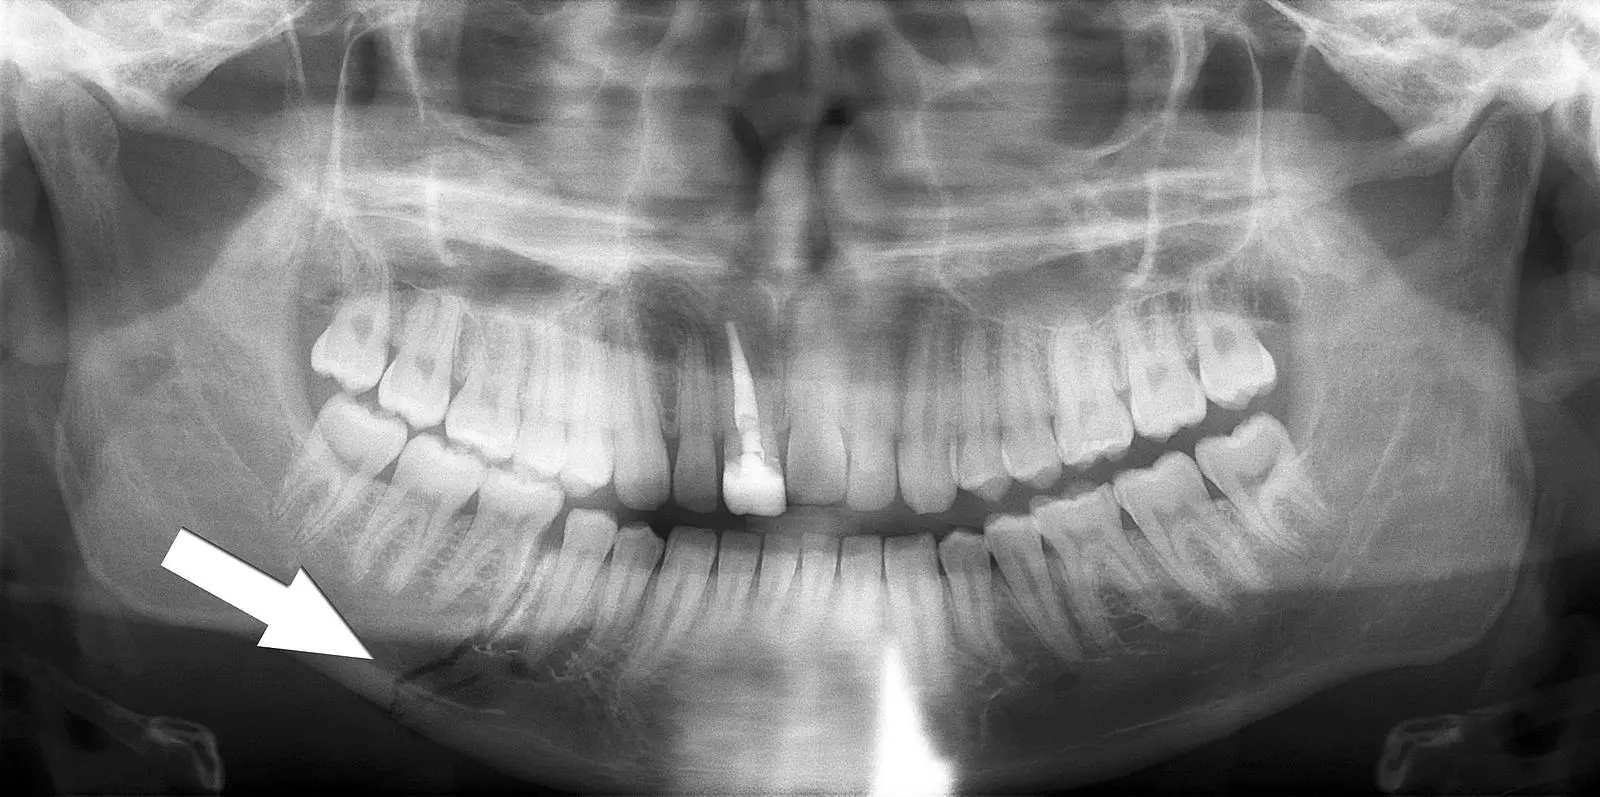

Fractures of the facial skeleton are common. The nasal bones are most susceptible due to their prominent nature on the face. The zygomatic arches and mandible are also commonly affected. The mandible is commonly fractured at more than one site due to its ring-like structure, often involving two fracture points.

Image - Orthopantomogram showing a fracture through the body of the mandible (indicated by the white arrow)

Creative commons source by Coronation Dental Specialty Group [CC BY-SA 4.0 (https://creativecommons.org/licenses/by-sa/4.0)]